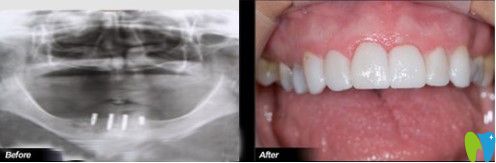

想了解沈陽(yáng)歡樂仁愛口腔做種植牙的效果如何?我們一起來瞧一瞧何先生做過種植牙之后案列吧!

何先生做過種植牙的案列圖

癥狀描述:何先生,46歲,因?yàn)檠乐軉栴}引起多顆牙松動(dòng),后來導(dǎo)致全口牙脫落。開始,何先生一直佩戴活動(dòng)假牙,但是很影響咀嚼和消化,長(zhǎng)期如此身體健康也受到了影響。

歡樂口腔醫(yī)生診斷:上下牙列缺失,全口牙齒只剩下上牙中一顆虎牙。

歡樂口腔治療方案:根據(jù)顧客的口腔內(nèi)部需求,決定植入4顆種植體,然后做覆蓋義齒修復(fù)。